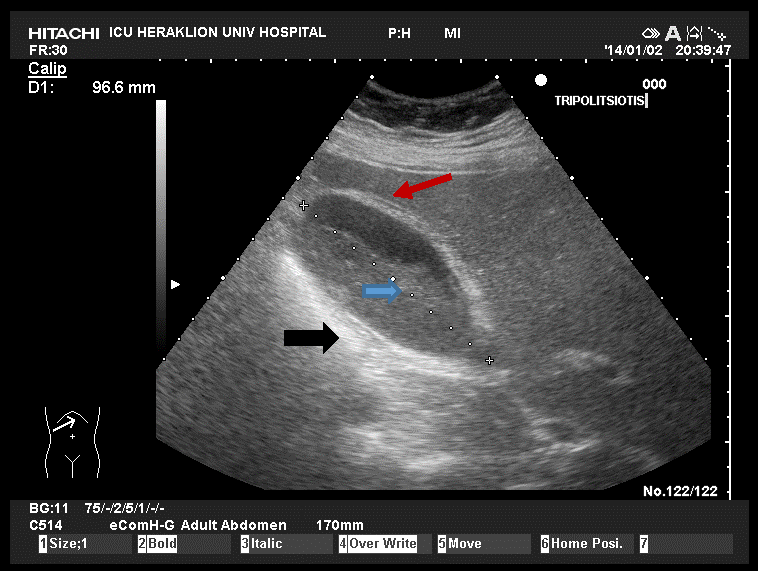

φλέβας. (Εικ. 13) [39] Εικ. 13. Χοληδόχος κύστη φλεγμαίνουσα, οριακών διαστάσεων, με πάχυνση

και διαστρωμάτωση του τοιχώματος

(βέλος μαύρο) σχεδόν πλήρης περιεχομένου (βέλος μπλε) και ελάχιστο περιχολοκυστικό υγρό, (βέλος